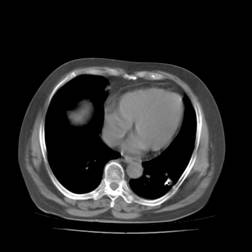

典型病例1:患者鞠xx,女,68岁,住院号:488141,因左胸痛1月余入院。2015年3月31日胸部增强CT示:左肺下叶2.5cmx2.8cm占位,左侧第三前肋骨溶骨性转移、形成厚约3cm肿块,左侧腋窝淋巴结2.1cmx4.1cm及前纵膈淋巴结转移。患者于2015年4月1日经CT引导下穿刺活检、病理证实为左肺下叶腺癌。于2015年4月5日对其采用125I放射性粒子置入治疗。治疗3个月随访,患者胸痛缓解,左肺下叶原发病灶消失,粒子聚集;左侧第三前肋骨基本恢复正常形态;前纵膈淋巴结消失,粒子聚集;左侧腋窝淋巴结缩小2/3。目前患者生活质量良好,可从事一般家务劳动。

术前CT片: